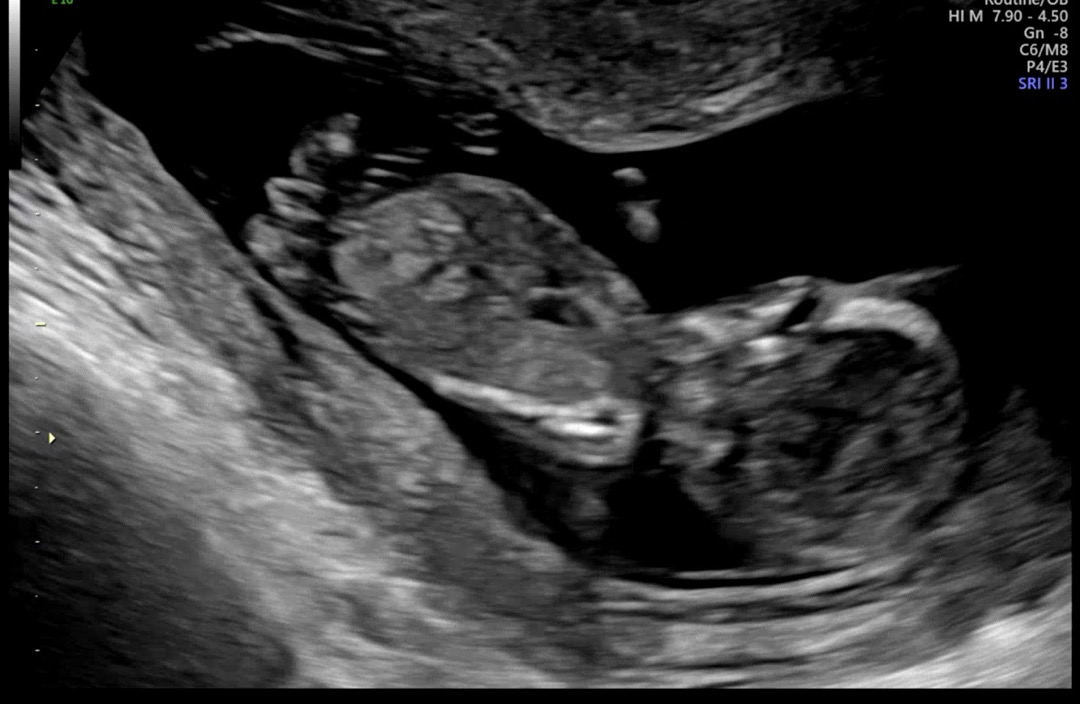

각도법 봐주세용 ㅎㅎ

잘안보이는거 같긴한데 ㅜㅜ 딸일까요 아들일까요